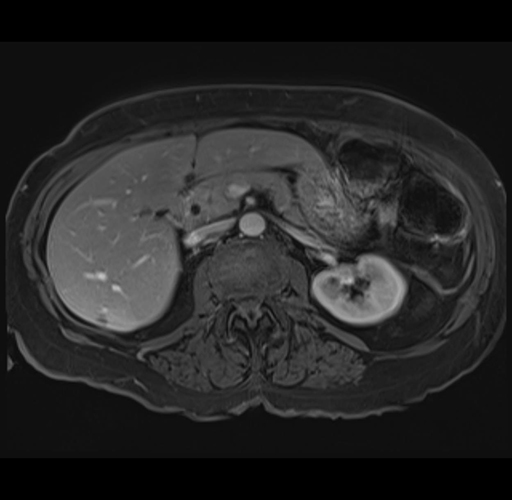

MRI T1

Imaging analysis

Based on your CT findings, which issue(s) would give reason for "planned slowing down moment(s)" in this case?

Considering a standard right hepatectomy procedure, what step(s) of the operation would you do differently in this case?